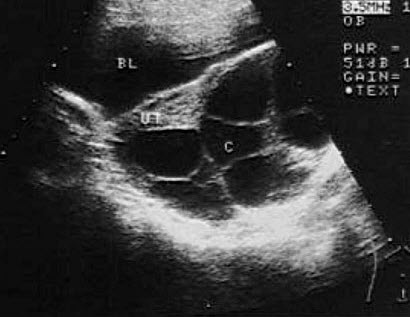

13、单项选择题

女,25岁,因急性胰腺炎禁食5天。声像图如图所示。结合超声声像图,诊断为()